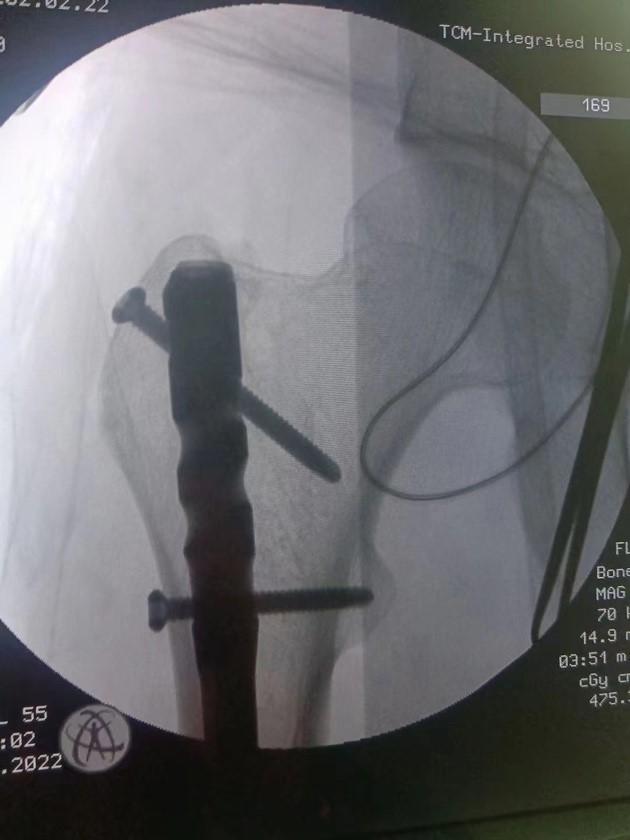

大年初二,王先生退热并且各项指标恢复正常,达到手术条件。术前,手术室杨嘉琪等护士为王先生精心摆好最合适的体位,在麻醉科医护人员的紧密配合下,骨伤科创伤足踝组组长徐楚江主任医师和科室骨干成功完成微创股骨干骨折闭合复位髓内针内固定手术治疗。

微创手术固定完成